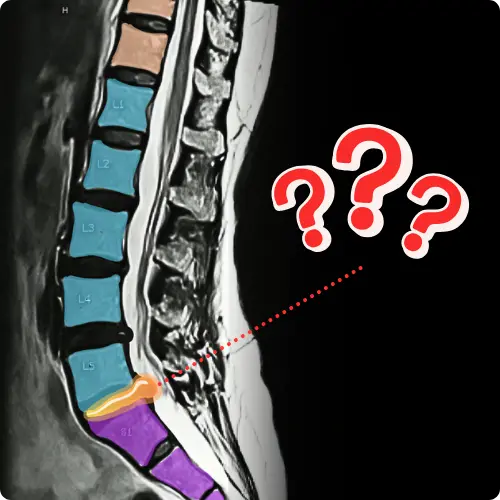

Here is a real MRI report from one of our clients:

"There is a posterior/left paracentral disc extrusion descending caudally measuring 17 x 8 x 11 mm resulting in impingement upon the descending left L5 rood in the left lateral recess and moderate narrowing of the thecal sac."

Does that sound familiar? It should. The MAJORITY of clients we work with have MRI findings similar to this.

As long as your doctor said it's safe to try PT or non

-surgical options, we can take it from there.This program has worked for people with:

- Disc herniations, extrusions, protrusions, bulges, and sequestrations (yes, even SEVERE)

- Nerve impingement- Stenosis

- Spondylolisthesis, anterolisthesis, and retrolisthesis- Scoliosis

- Degeneration (arthritis)

- And many other conditions...